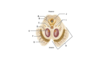

What part of the spinal column is this?

Cervical

What part of the spinal column is this?

Thoracic

What part of the spinal column is this?

Lumbar

What part of the spinal column is this?

Sacral

How do you identify where from the spinal column a section comes from?

Cervical - thin and pointy

Thoracic - thin and pointy, smaller than cervical

Lumbar - thick

Sacral - thickest, more geometric than lumbar